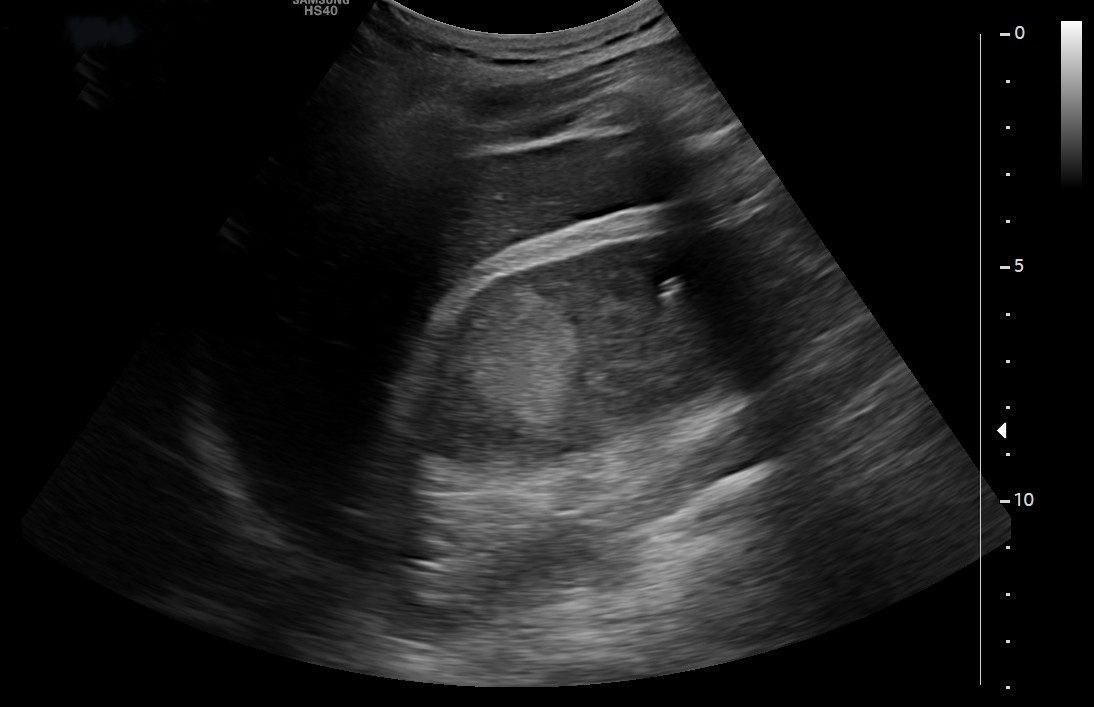

Se realiza ecografía para valorar tamaño prostático.

Hallazgos ecográficos

Hallazgos ecográficos: lesión sólida exofítica de márgenes bien definidos en la región interpolar posterior del riñón derecho, hiperecogénica respecto a la cortical renal, con vascularización interna en el estudio Doppler y unas medidas aproximadas de 45 x 40 mm.

Próstata aumentada de tamaño, con unas dimensiones de 55x65x56 mm que se corresponden con un volumen de 106 cc (hipertrofia prostática grado IV).